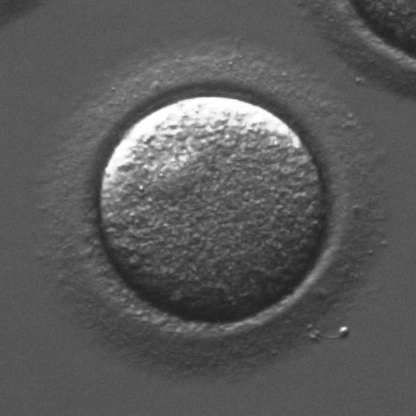

Infertility is becoming an issue for an increasing number of couples. The most common solution, in vitro fertilization, requires embryologists to carefully examine light microscopy images of human oocytes to determine their developmental potential. We propose an automatic system to improve the speed, repeatability, and accuracy of this process. We first localize individual oocytes and identify their principal components using CNN (U-Net) segmentation. Next, we calculate several descriptors based on geometry and texture. The final step is an SVM classifier. Both the segmentation and classification training is based on expert annotations. The presented approach leads to a classification accuracy of 70%.